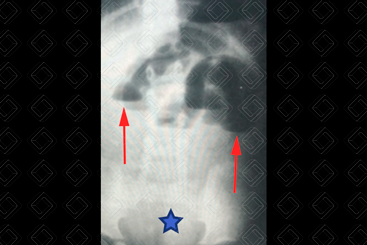

Texto alternativo para a imagem Figura 1. Créditos: Dra. Elazir Mota - Rio de Janeiro/RJ

Descrição das figuras 1 e 2: Radiografia de abdome em decúbito e ortostase. Há sinais sugestivos de um quadro obstrutivo, como ausência de gás no reto (asterisco), níveis hidroaéreos em alturas diferentes (setas vermelhas) e o padrão chamado de alça em “U” invertido (setas amarelas). Nesse, caso trata-se de uma provável obstrução de alças de delgado (as alças estão dispostas mais centralmente na radiografia e isso sugere acometimento mais alto, ou seja, de intestino delgado).